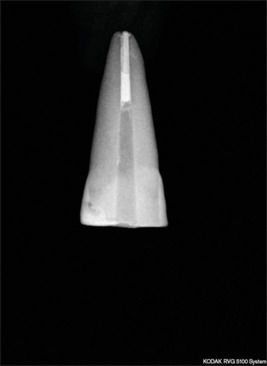

Materials and methods: For this comparative in vitro analysis, postspace was prepared in 15 recently extracted teeth and impressions made with vinyl polysiloxane, polyether (PE), vinyl polyether silicone (VPES), and pattern resin. Postpatterns obtained were re-seated on the teeth and longitudinally sectioned. A binocular microscope was used to measure apical and lateral discrepancies at three locations (L1, L2, and L3). L1 at the postcore junction, L2 at the middle of the post space, and L3, 2 mm short of the apical end. The data obtained were statistically analyzed using the Statistical Package for the Social Sciences (SPSS) software. One-way analysis of variance (ANOVA) (intergroup) followed by Tukey's post hoc test with P ≤ 0.05 was used.